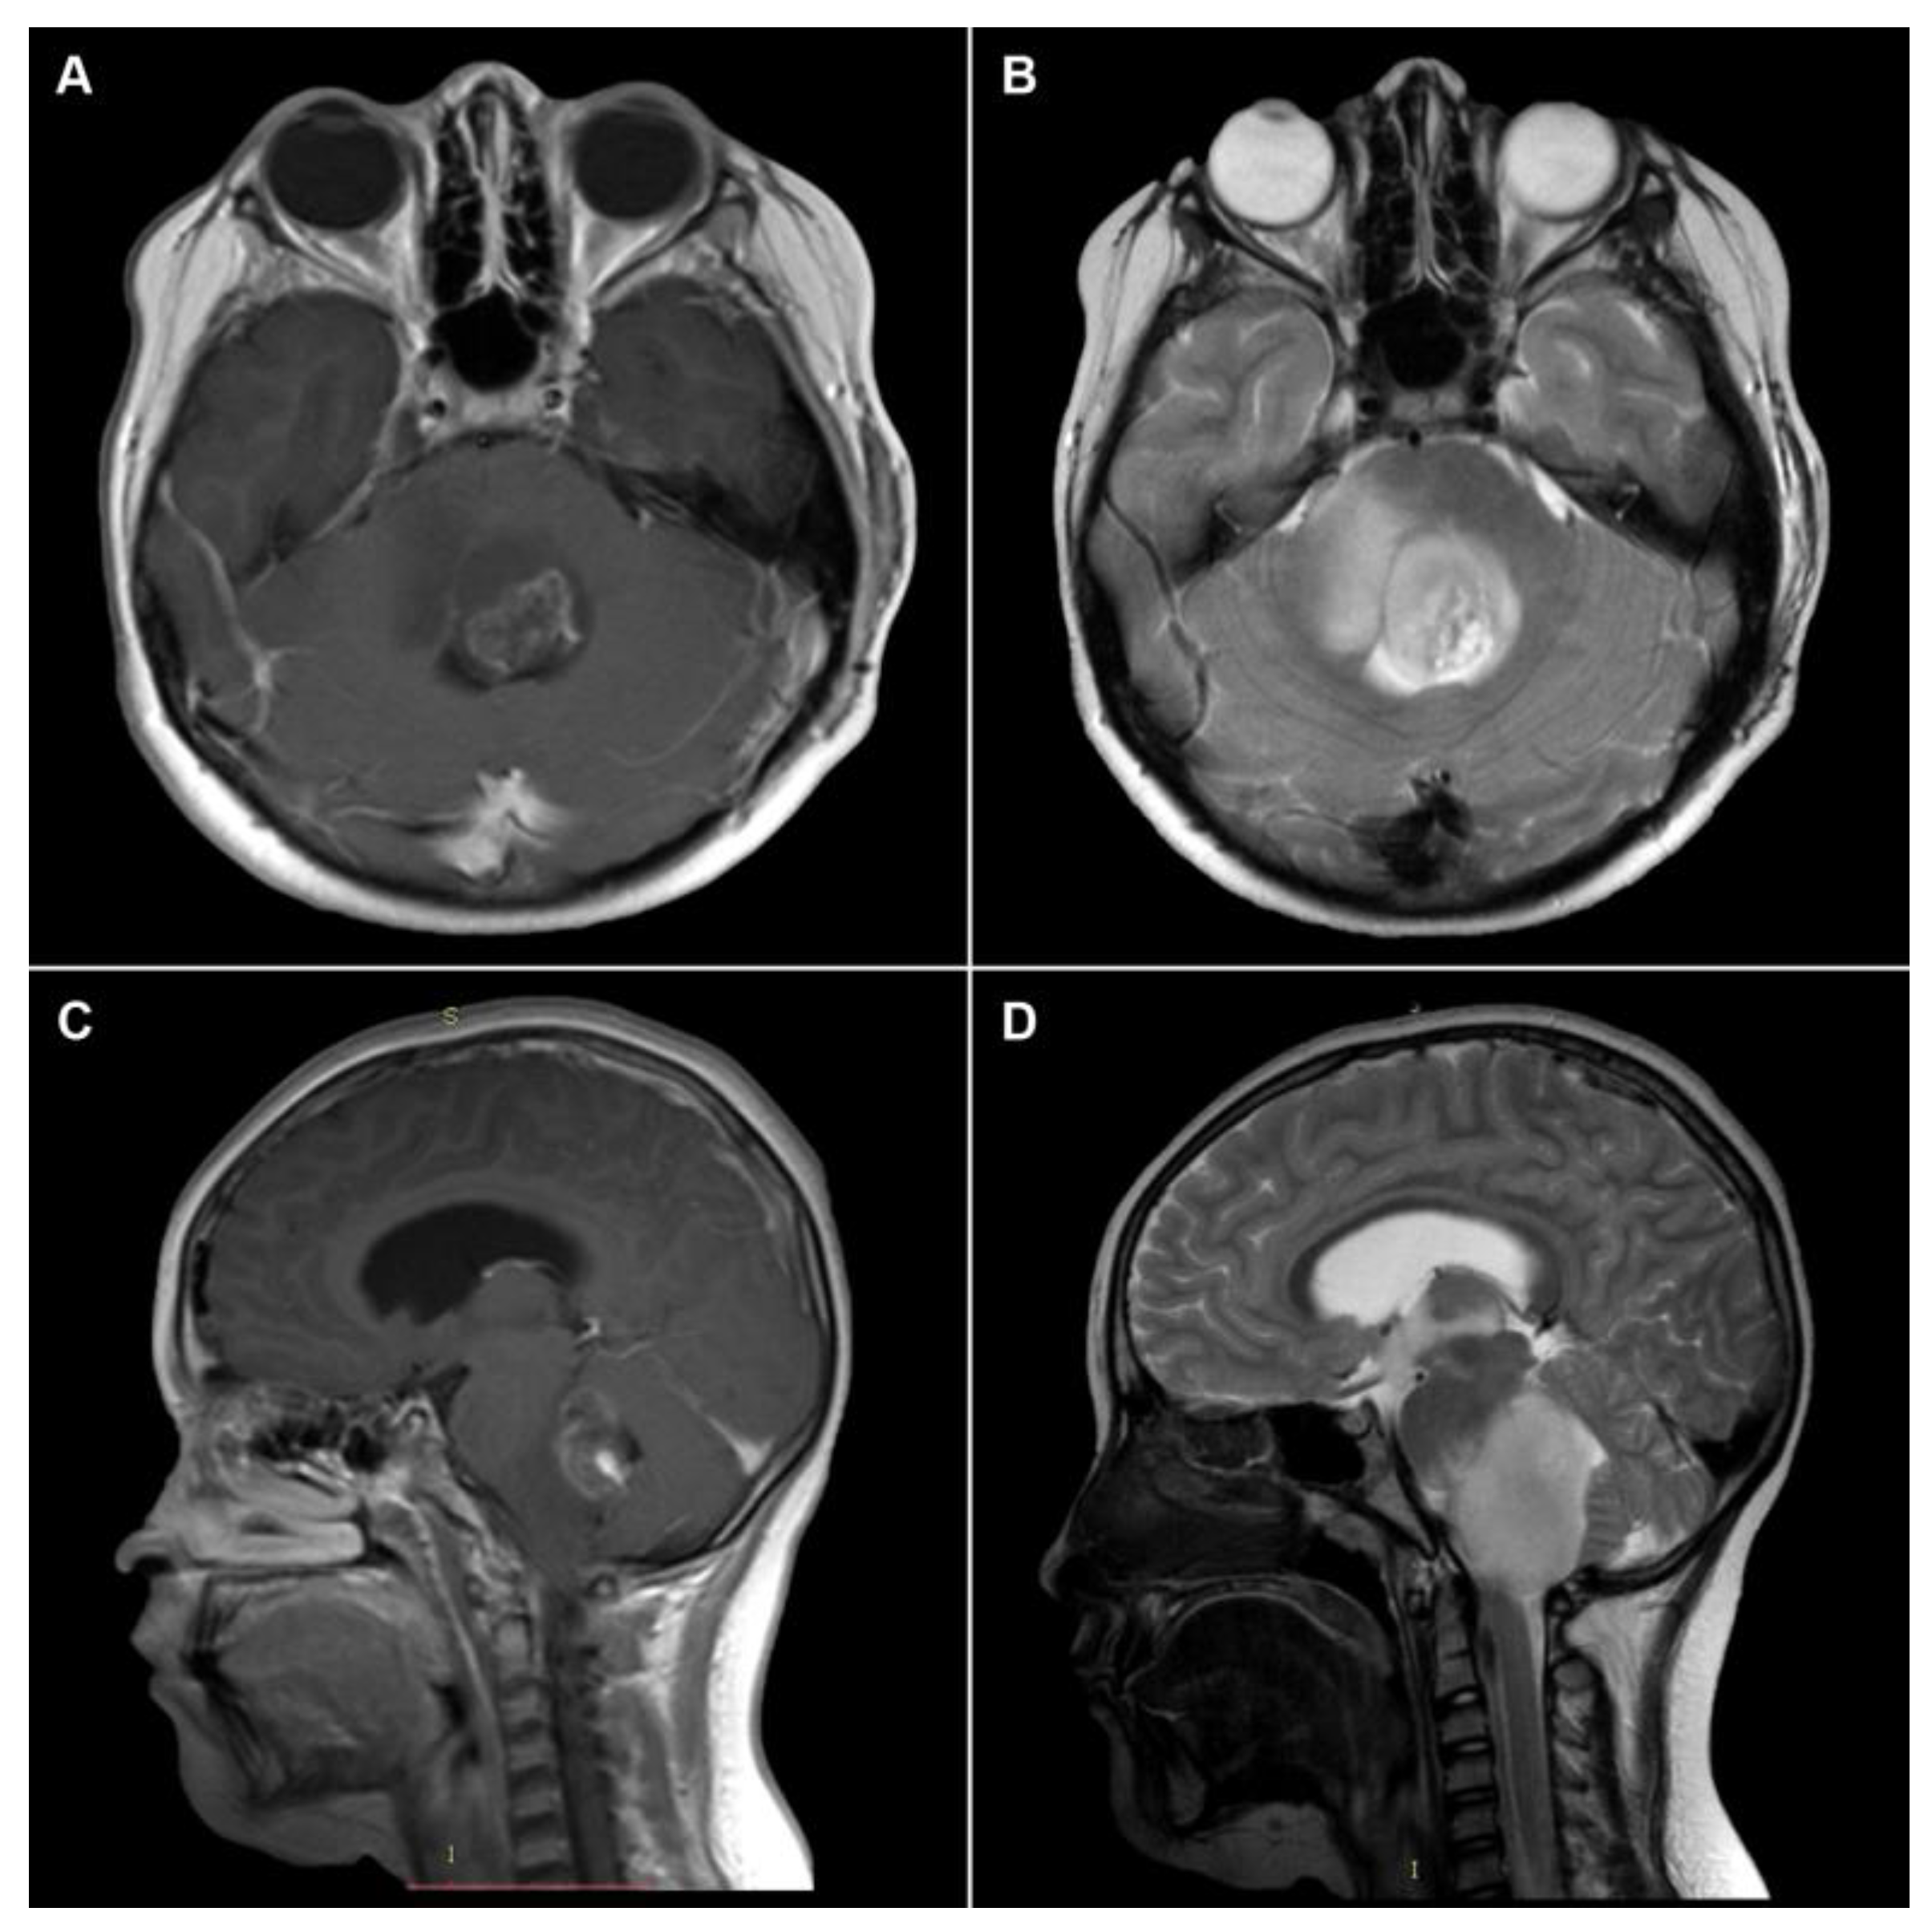

2.1. Imaging Evaluation of Midline Gliomas